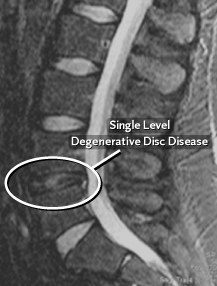

In many situations, doctors will order a MRI or a CT scan (CAT scan) to evaluate the degenerative changes in the lumbar spine more completely. A MRI is very useful for determining where disc herniations have occurred and where the nerve roots are being compressed. A CT scan is often used to evaluate the bony anatomy in the spine, which can show how much space is available for the nerve roots and within the neural foramina and spinal canal.